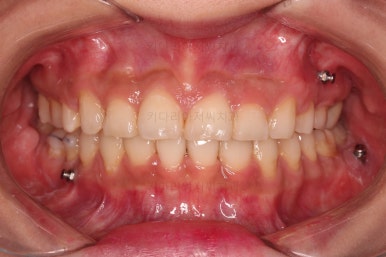

연산동교정치과 전후 비교해 보겠습니다.

얼굴모습도 약간 나와있던 윗입술 느낌도 완벽히 개선되었고요.

전반적으로 깔끔하게 임플란트 없이 결손치아 부분을 잘 마무리 했습니다.

이상 결손치아가 있을 때 미니스크류를 이용해 임플란트 없이 사랑니를 당겨와 치료한 연산동교정치과 치료사례였습니다.